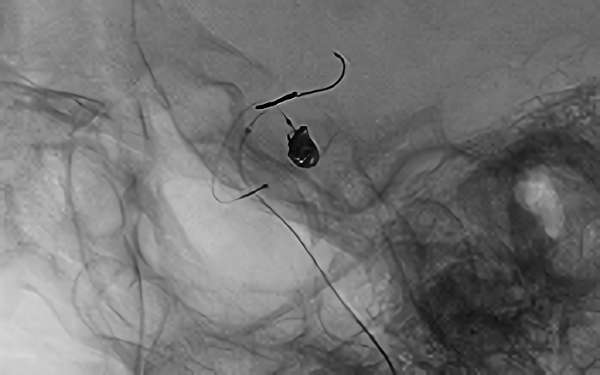

No.1628 手術中